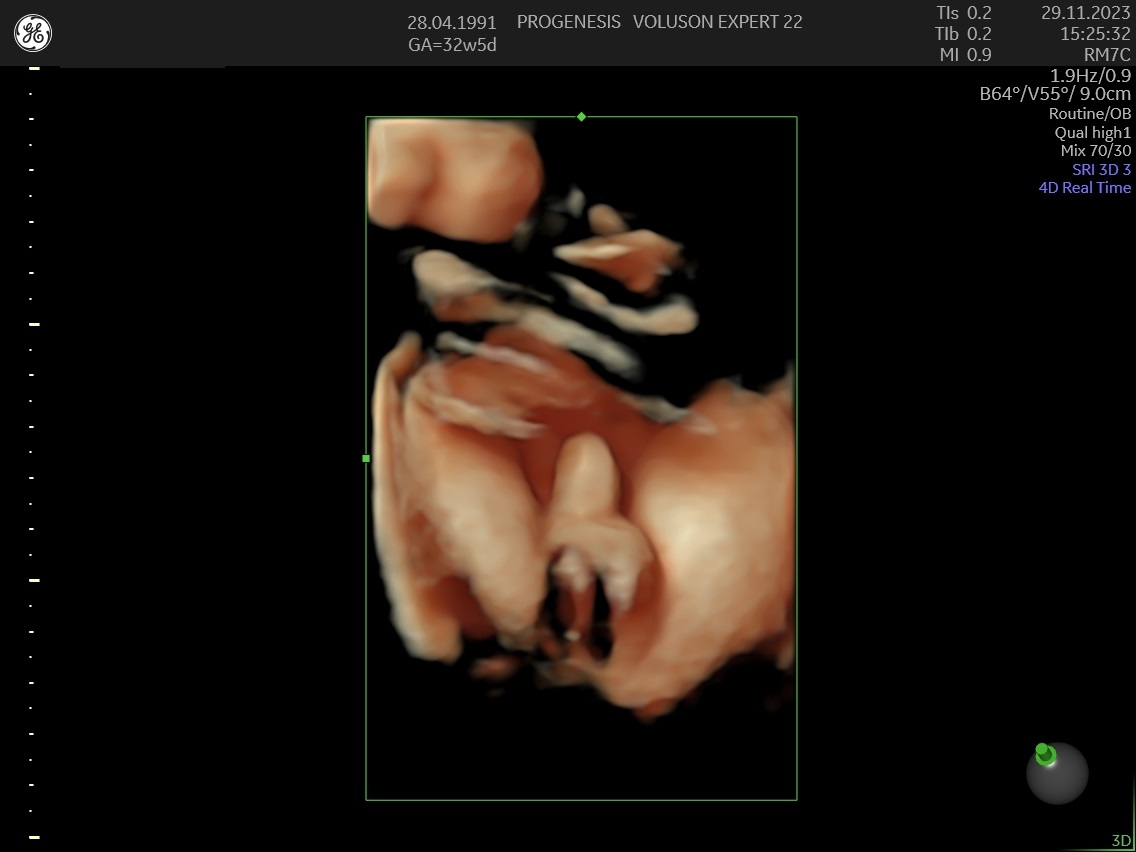

Το 3D/4D LIVE είναι μια νέα τεχνολογία υπερήχων που δημιουργεί εικόνες του εμβρύου σε τρισδιάστατο ή τετραδιάστατο χώρο. Οι εικόνες αυτές είναι πιο ρεαλιστικές από τις παραδοσιακές εικόνες υπερήχων και δίνουν στους γονείς μια πιο ολοκληρωμένη εικόνα του μωρού τους.

Σε πιθανά ανατομικά προβλήματα του εμβρύου μπορούν να βοηθήσουν στην κατανόησή τους από τους γονείς.

Ωστόσο, οι εικόνες 3D/4D LIVE δεν μπορούν να αντικαταστήσουν τις παραδοσιακές εξετάσεις υπερήχων.